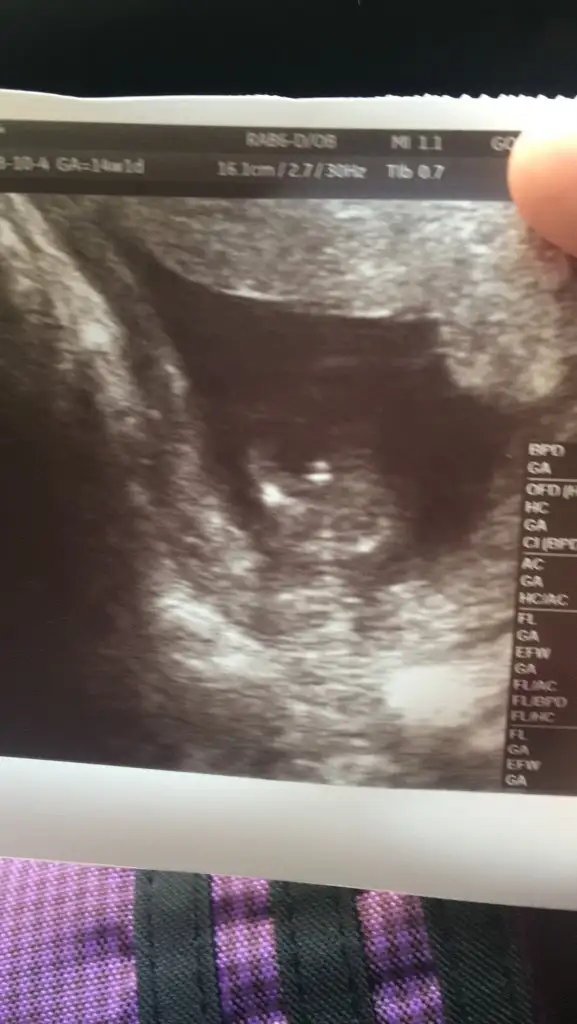

Günaydın kızlar valla su cinsiyet meselesi yedi bitirdi beni

doktor erkeğe benziyor deyip gecistirmisti devlette

O kadar çok erkek bebek ultrason resmi gordum ki rüyama girmiş ultrasonda kocaman çıkıntı görüyoruz

galiba benimkide erkek rüyasında görüp cikan varmi uoksa psikolojik mi